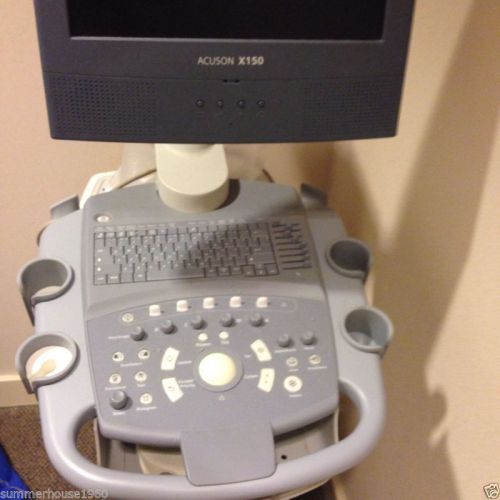

Ultrasound Siemens Acuson X150 Ultrasound Model A91US-161-1C-4A00